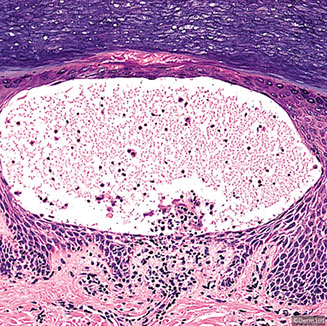

Bullous pemphigoid

Micro: Subepidermal blister (bullae) c eos and sometimes neutros in blister cavity

IF: Direct IF in perilesional tissue shows IgG and C3 on DE junction (basement membrane) in linear or n-serrated pattern